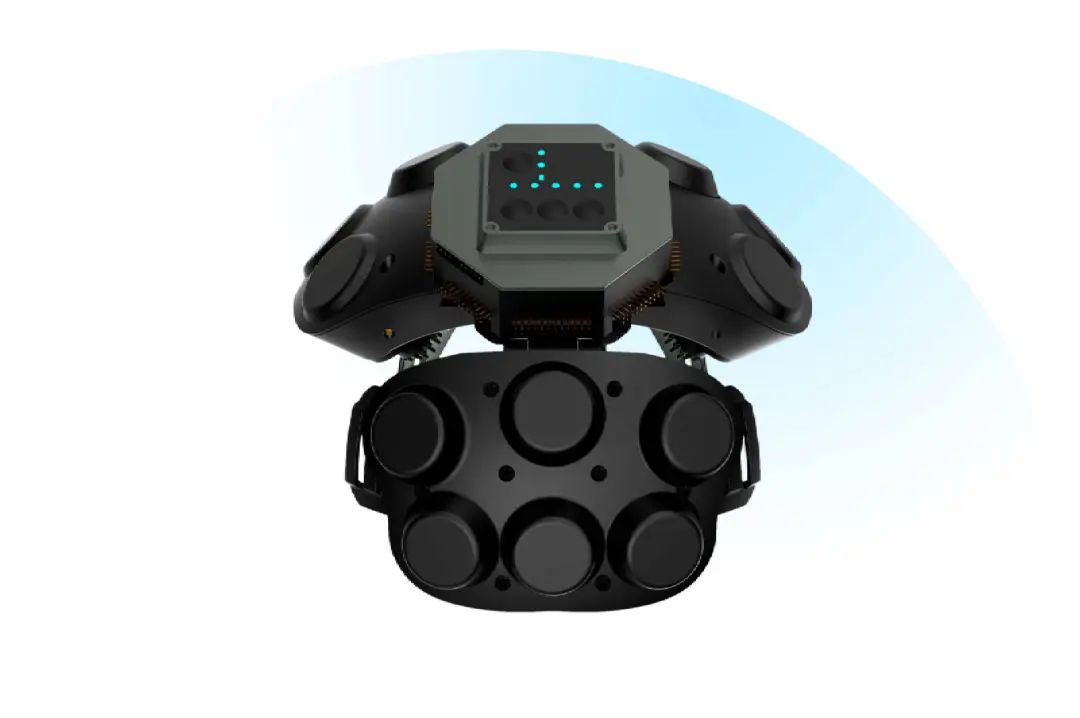

回映产品:AR-BCI智能脑控头盔

AR-BCI智能脑控头盔采用创新干电极技术,通过弹簧式接触结构(触角直径2mm,数量10-15根)无需凝胶即可稳固贴合头皮,适合24小时连续监测,提升佩戴舒适度和稳定性,并能精准捕捉短暂异常放电及区分正常变异脑电信号如Mu节律和Wicket波,防止误诊。设备具备≥130dB的共模抑制比和>1000MΩ的输入阻抗,有效抑制干扰,确保信号采集高精度与可靠性,同时实时阻抗检测与脱落提示功能减少漏检风险。该头盔集成了AR显示、眼动追踪和多模态脑电采集功能,支持同步分析脑电与行为数据,特别适用于异常放电捕捉和复杂正常变异脑电信号识别。

适应症:康复科、神经内科、神经外科、卒中中心、老年科。

干电极的

参数

交流阻抗:阻抗≤1000Ω;

直流失调电压: 电压≤100mV;

内部噪音: 电压<150uv;

除颤过载回复: 变化率<±1mV/s、除颤后阻抗<1000Ω;

偏置电流耐受度: 电压变化<100mV。

采集系统

采样率:≤16KSPS,每个通道独立可控制;

共模抑制比:≥120dB;

系统噪声:≤5uVrms;

模数转换率:24位;

输入信号范围:±375mVpp;

采集通道有8路/16路/32路,支持单极性采集,预留双极性采集方案;

具备8路/16路/32路电极阻抗检测功能,并实现电极脱落指示功能;

输入阻抗>1000Mohm、输入噪声<0.15uVRMS(0.5~70Hz)、共模抑制比 CMRR ≥ 130dB,达到 JJG954—2019《数字脑电图仪检定规程》相关指标要求;

电极尺寸:电极盘直径18mm,触角长度6.5mm,触角直径2mm,触角数量10~15根。弹簧式干电极结构,保证电极与头皮贴合紧实,前额可安置心率血氧模块。